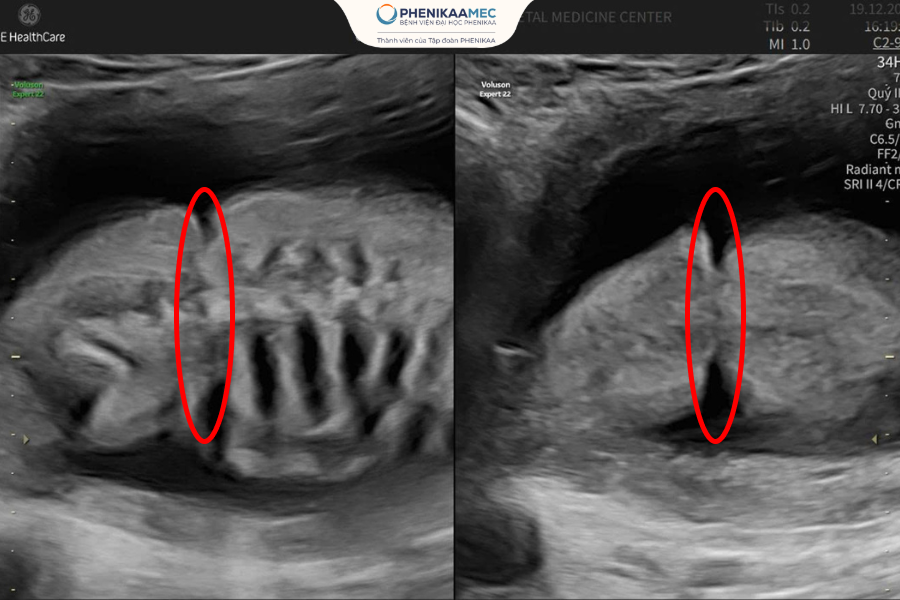

Hình ảnh siêu âm cho thấy dải xơ buồng ối thắt ngang bụng của thai nhi

Ở tuần thai thứ 21, chị L.N.K.Q (29 tuổi, TP.HCM) nhận kết quả siêu âm cho thấy thai nhi xuất hiện dải xơ buồng ối - một bất thường hiếm gặp có thể dẫn đến biến dạng chi, hoại tử, thậm chí tử vong trong tử cung. Trước nguy cơ này, gia đình chị được tư vấn đình chỉ thai kỳ nhằm tránh những rủi ro khó lường. Thế nhưng, ngay trong khoảnh khắc mong manh nhất, chị vẫn níu giữ một hy vọng rất nhỏ. “Lúc đó tôi gần như suy sụp. Nhưng tôi nghĩ nếu còn một cơ hội nhỏ thôi, mình cũng phải thử,” chị Q. chia sẻ.